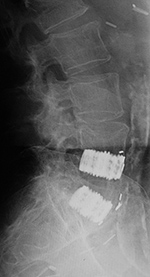

Thoracolumbar stabilization rods have a long record of success and are among the most commonly used spinal stabilization apparatus. They do have the disadvantage of their sublaminar hooks, which can compress the thecal sac or directly harm the neural roots or even the spinal cord. In the lumbar spine, they also tend to cause a loss of the normal lumbar lordosis (the so-called flat-back syndrome), which may produce disabling chronic pain over time. Pedicle fixation systems were designed to overcome these problems. In these fixation systems, screws are placed through the pedicles into the vertebral bodies. The screws are connected together on each side, with rods or a plate placed over the pedicle screws on each side. There are many variations on this common design, with several systems now available, including the Steffee, Edwards, Roy Camille, and Cotrell-Dubousett devices (figure: lumbar pedicle screws and rods; figure: Brantigan intervertebral cage; figure: Steffee plates and screws; figure T12-L2 pedicle screws and rods).

The Steffee design is very common. It uses flat plates to connect

the screws, whereas the Cotrell devices use rods to connect to the screws. The TiMx Comprehensive Low Back System is a titanium system composed of pedicle screws, spine plates, washers, rods, slotted connectors, and a cross connector (figure: posterior spinal fusion). Most of these systems are combined with posterolateral “bony fusion masses” (osseous grafts) composed of bone pieces or bone shavings taken from the iliac crest tuberosity on one or both sides. The bony fusion masses are packed around the fixation devices, and in 4–5 months they evolve to become solid masses of mature bone. The fusion of bone provides the ultimate stability for the spine. If fusion is not successful, the fixation apparatus often eventually fails, with breakage or loosening of components.

| Steffee pedicle plates and screws |

| Frontal and lateral views in two different patients show bilateral Steffee plates and screws in the lumbar spine with two side by side Brantigan intervertebral cages (arrows) at L2-3. |